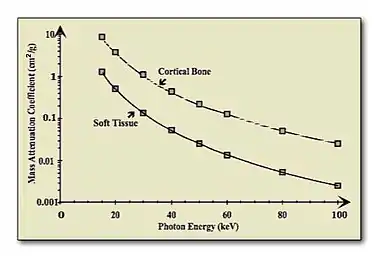

- Dual-energy imaging is based on exploiting the difference in the attenuation of tissue and bone - see Figure 7.16 - at different X- ray energies. It generally involves acquiring images at two X-ray energies and processing them to suppress either the bone or the tissue information. A simplified mathematical model, similar to that developed earlier earlier for DSA, assumes that monoenergetic radiation is used and no scattered radiation, once again, is detected, so that the transmitted radiation intensity through a region of bone and tissue, acquired at a low X-ray energy and following logarithmic transformation, can be given by: